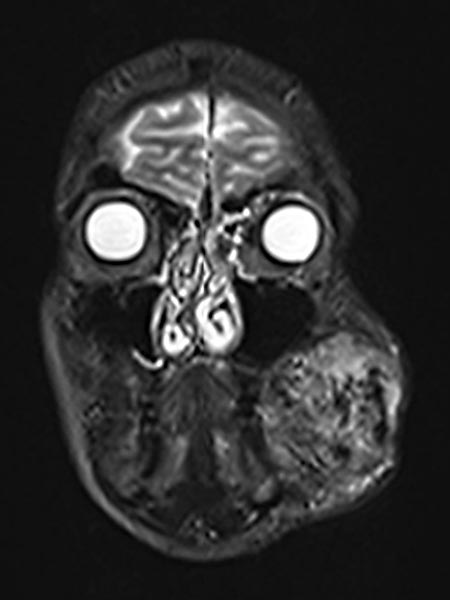

Axiale, T2-gewichtete MRT auf Höhe der Wange zeigt die AVM relativ hyperintens mit Ödem des Gewebes und Ausdehnung bis zum linken Unterkiefer. Im rostralen Abschnitt auch einige schwarze flow-voids durch stark durchblutete Arterien innerhalb der AVM.

Inhomogenes, vor allem peripheres Enhancement der proliferierenden AVM in dieser axialen fettunterdrückten T1-gewichteten MRT nach Kontrastmittelgabe. Keine abgrenzbare, eigentlich solide Komponente, anders als bei einem echten vaskulären Tumor.